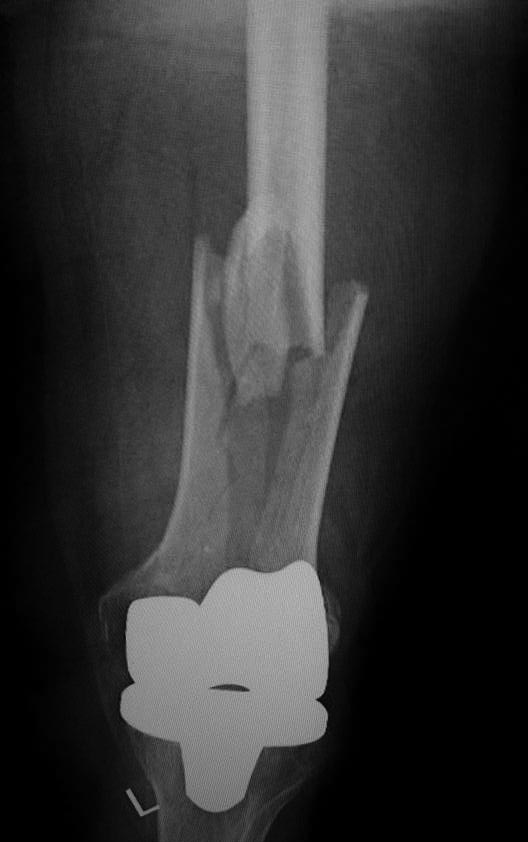

эКак оказалось в нашей ЦРБ сделали уже сегодня шеф решил без СТ. Пациент 41 года с большим количеством патологии. То есть полных 76 лет.

Норм остеосинтез но я в данном случае только за аппарат

Принципиальный момент- стабилен ли бедренный компонент? Если компонент изначально стабилен, что в данном случае мало вероятно), то все ок. Наилучшие результаты при использовании ИМ остеосинтеза (хотя могут быть проблемы с репозицией и размером гвоздя), затем блокированные пластины, затем все остальное ( последнее время много статей про применение аппаратов наружной фиксации). В данном случае длинна пластины корректная, но в зоне перелома слишком много металла, выше перелома должно быть 4-5 винтов, все бикортикально, с чередованием с пустыми отверстиями. То, что внизу торчат винты не очень good, но не так страшно. Консервативное лечение сопряжено с высоким риском летальности в течение первого года после травмы, вполне сравнимым с не оперированными шейками. Ключевой вопрос - стабильность бедренного компонента, теперь риторический).

А что правда кто-либо считает этот остеосинтез хорошим? По-моему беда! Шансов на сращение крайне мало, а для пожилого человека это может быть конец. Все принципы нарушены...

76 лет, остеопороз. В таких условиях требуется максимальное сохранение кровоснабжения в зоне перелома и фиксация с соблюдением принципа шинирования. Оно может быть накостным, интрамедуллярным или при помощи АНФ. В данном случае операция открытая, очень травматичная, куча винтов в зоне перелома, которые там неизвестно зачем, ну и серкляжи, которые могут стать последней каплей в убийстве кости. Из хорошего это действительно длина пластины, но при таком расположении винтов она (длина) не работает

Скорее всего, бедренный компонент не отклеился, так что это Rorabeck-Lewis II. Традиционный вариант - пластина с угловой стабильностью закрыто. Или две, чтобы от варусного коллапса подстраховаться. Мне больше бы импонировал антеградный закрытый интрамедуллярный остеосинтез.

1. Чаще всего у пациентов этого возраста перипротезный перелом после ЭПКС - последствие низкоэнергетический травмы на фоне выраженного остеопороза. Т.е. согласен с Михаил Панин, что следует поберечь кровоснабжение.

2. При определении тактики лечения таких пациентов, если оперативное лечение конечно возможно, ключевыми являются два фактора: стабильность бедренного компонента и размер дистального фрагмента. Если бедренный компонент нестабилен об остеосинтезе речи быть не может.

4. Принципы мостовидного остеосинтеза на показанных картинках не реализованы, в этом Панин безусловно прав.

Количество эндопротезирований растёт, поэтому с подобными случаями придётся сталкиваться чуть не каждому из нас. Или каждому. Думаю, следование принципам - абсолютная стабильность вокруг компонентов протеза и относительная - вне, не может вызывать особых дискуссий.

К сожалению (при этом желаю и хирургу, и пациенту удачи), выполненное вмешательство оставляет крайне мало шансов больному. Именно потому, что для метадиафизарной части перелома доктор пытался добиться абсолютной стабильности. Что не приемлемо при остеопорозе. Там и случится проблема, возможно, в самое ближайшее время. Я бы использовал остеосинтез пластиной - миниинвазивный для метадиафизарной зоны (как я понимаю, мы предполагаем, что ножка стабильна? ОК). Вот эти винты и завитушки на диафизе лишние и только демонстрируют не вполне гуманное отношение к биологии в этой зоне.

Учитывая, что протез без стабилизатора, межмыщелковое пространство абсолютно свободно и оптимальным вариантом в данном случае мог стать ретроградный интрамедуллярный остеосинтез с блокированием как самый малоинвазивный и сохраняющий и без того того повреждённое кровоснабжение через надкостницу. Выполненный накостный остеосинтез нельзя отнести к стабильному, к тому же по представленным рентгенограммам складывается впечатление, что винты проведённые через мыщелки обычные кортикальные, не фиксированы в пластине, серкляжные швы не придают стабильности. Потребуется длительная контролируемая реабилитация. Не исключается по результатам рентгенконтроля повторное оперативное вмешательство (костная пластика или всё-таки переход на интрамедулляный остеосинтез)